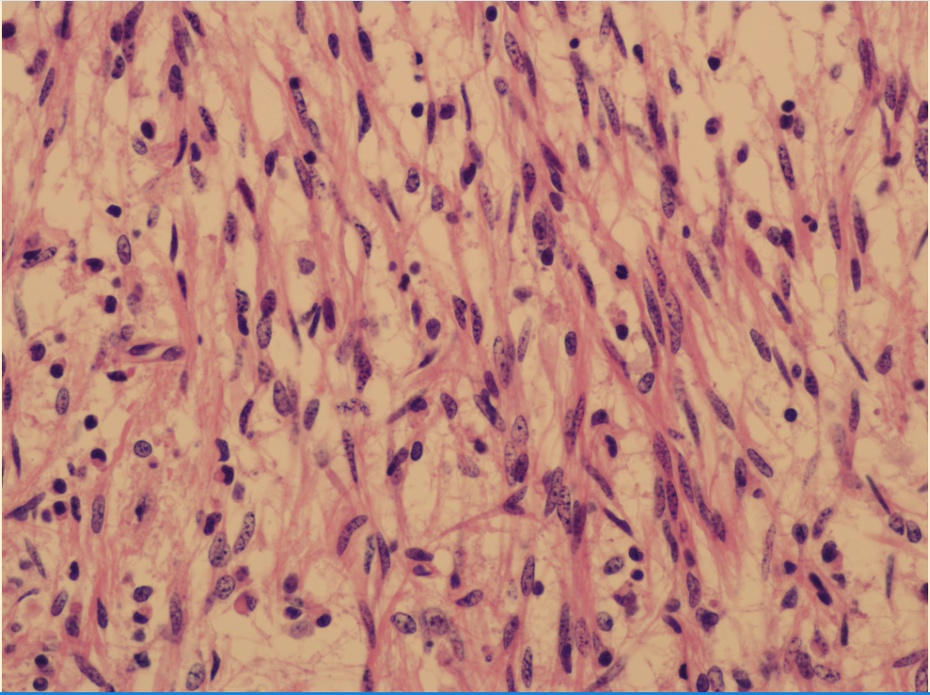

术后病理显示:视神经毛细胞型胶质瘤

少儿视神经胶质瘤分析:本病相对少见。瘤体可为单侧、双侧,可累及视交叉,甚至视束、视放射。患儿进行性视力减退,瞳孔反射性扩大,故患儿瞳仁多较大显得又黑又亮。随瘤体增大,视丘下部受累可出现多饮多尿表现,脑室系统堵塞可伴发脑积水。瘤细胞以毛细胞型为多,发展缓慢。本瘤对化疗和放疗均不敏感。彻底的切除肿瘤,常会造成视力完全丧失,故不足以取;部分活检以明确诊断,是通常认可的办法。实际上,目前对视神经胶质瘤尚缺乏缺乏有效的保守型治疗措施。我们祈祷这些患儿随着医疗科学的进步能有一天获得视力的重生。 #挑战30天在头条写日记#